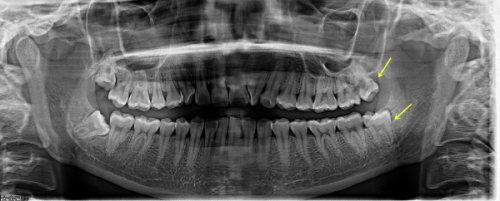

口腔疾病的预防和早期诊断至关重要。在钦州市第二人民医院口腔科,诊断与预防类项目丰富多样。拍牙片是常见的检查方式,普通小牙片可用于检查局部几颗牙,费用在20 - 50元;全口曲面平展片能进行全牙列检查,价格在100 - 150元;三维口腔CT则是种植或矫正前的必备检查,收费200 - 300元。洗牙与牙周治疗也特别关键,超声波洁牙作为基础清洁,39.9元起;喷砂洁牙可去除色素,150 - 200元起;牙周刮治针对牙龈问题,300元起/区域。这些项目能帮助患者及时发现口腔问题,预防疾病的进一步发展。